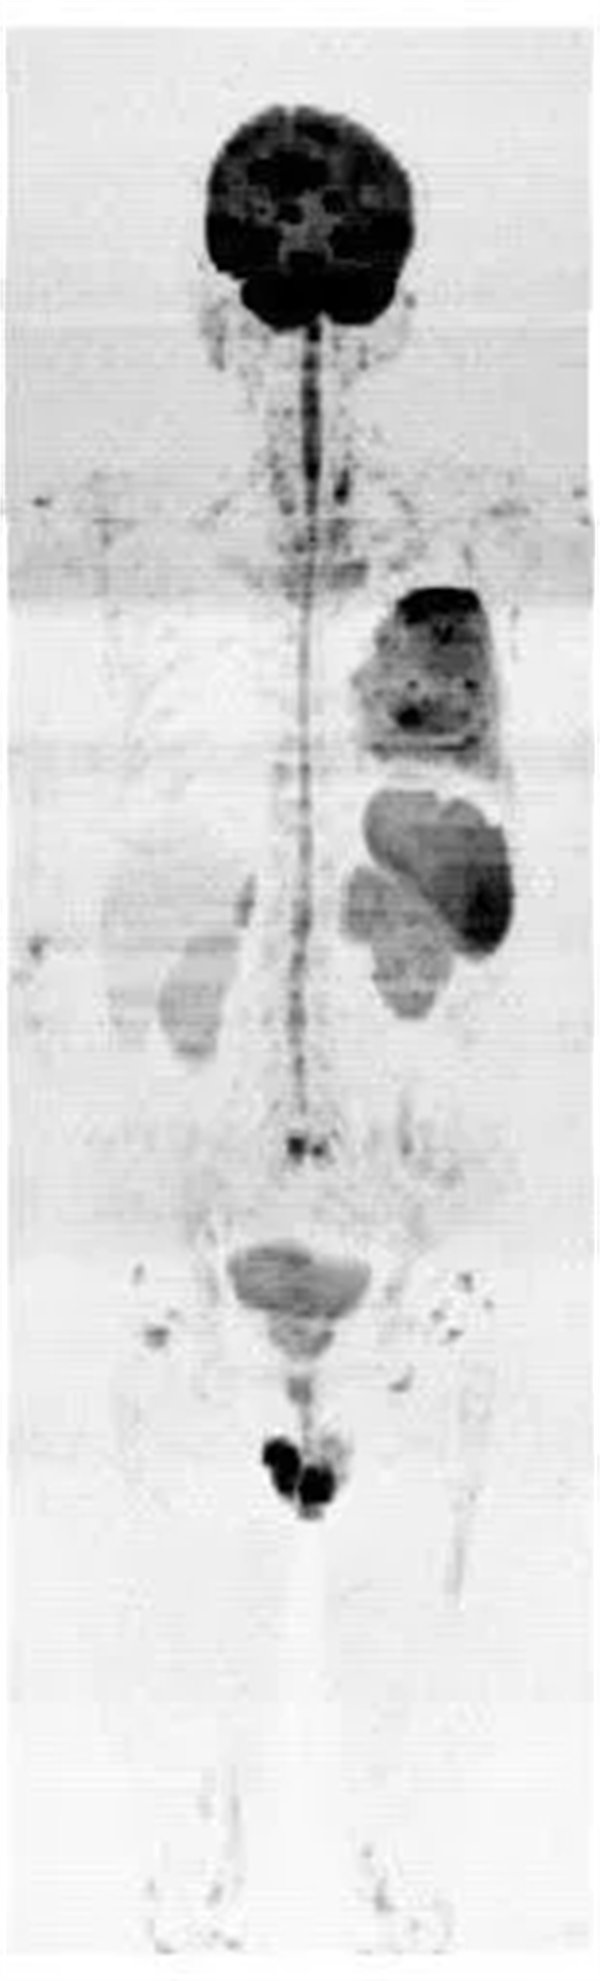

患者,男,左肺病變,為了查找全身有無其它病灶,明確分期,制定最合適的診療方案,臨床醫生決定行“類PET”即全身磁共振彌散成像(WB-DWI)檢查。

圖2:全身彌散成像反轉圖

磁共振全身彌散加權成像(WB-DWI),是將彌散加權成像技術與自動拼接技術和全景成像矩陣相結合而獲得全身的彌散加權成像影像。所得影像經黑白翻轉后可達到與正電子發射計算機體層顯像(PET)影像類似的效果,故被稱為“類PET”,是近年來發展起來的全新影像檢查新技術。

該技術能夠進行全身大范圍掃描,并加以3D后處理重建,可獲得全身腫瘤篩查、良惡性腫瘤的鑒別、腫瘤TNM分期及療效隨診等診斷信息,全身彌散技術把肌肉、脂肪、肝臟等組織背景信號抑制掉,突出了病變的顯示,大大提高了病變組織尤其是惡性腫瘤及其轉移灶的檢出率。